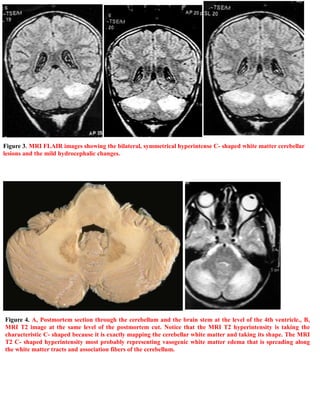

This document summarizes a case study of a 6-year-old male patient who presented with cerebellar ataxia and headache 3 weeks after a viral infection. Clinical exams revealed trunk and limb ataxia, nystagmus, and papilledema. Brain scans showed bilateral symmetrical lesions in the cerebellar white matter. The patient was diagnosed with acute postinfectious cerebellitis and fully recovered within a week of supportive treatment. The case study is intended to demonstrate the characteristic MRI findings of postinfectious cerebellitis.